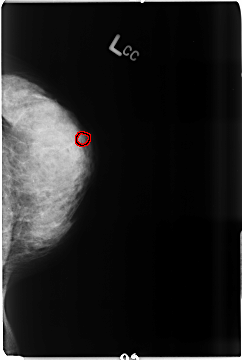

B_3516_1.LEFT_CC

FILE: B_3516_1.LEFT_CC.OVERLAY

TOTAL_ABNORMALITIES 1

ABNORMALITY 1

LESION_TYPE CALCIFICATION TYPE PLEOMORPHIC DISTRIBUTION CLUSTERED

ASSESSMENT 4

SUBTLETY 3

PATHOLOGY MALIGNANT

TOTAL_OUTLINES 1

BOUNDARY